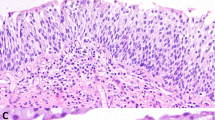

It was the most commonly found lesion (69 cases). The majority were non-keratinizing (57 cases) and the features were variegated: simplex or usual type (Figure 1a), 26 cases, hyperplastic, 12 cases, clear cell, 11 cases and with spindle cell features, eight cases. Most cases of clear cell metaplasia showed a particular segmental distribution in small intraepithelial nests or islands surrounded by normal urethral epithelium (Figure 1b). Sometimes these clear islands had a polypoid configuration protruding into the urethral lumen. Two cases showed diffuse clear cell metaplasia of the urethral epithelium (Figure 1c) extending to Morgagni's lacunae (Figure 1d). Keratinizing or hyperkeratotic squamous metaplasia was observed in 12 cases. There was surface hyperkeratosis, often associated with hyperplasia (Figure 1e). The hyperkeratotic squamous hyperplasia was associated in four cases with verrucous squamous cell carcinomas of the penis. In four specimens, in addition to squamous metaplasia, there were stromal changes consistent with lichen sclerosus (Figure 2). The lesions were extensions of lichen sclerosus affecting the glans penis.

In 14 cases the urethral epithelium showed focal atypical intraepithelial changes. In low-grade SIL (eight cases), the atypical cells involved the lower half of the epithelium (Figure 3). In high-grade SIL (six cases), the atypical cells involved the entire epithelial thickness (Figure 4a, b). The majority of the intraepithelial neoplastic lesions were discontinuous with the main penile invasive cancer, but a few were continuous.